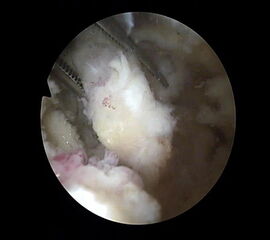

Abbildung Nr. 11-13

Das Os trigonum wird aus dem Weichteilgewebe gelöst und anschließend mit einer Fasszange entfernt. Bei größeren Knochenfragmenten muss ggf. das mediale Arthroskopieportal um wenige Millimeter verlängert werden, um die Extraktion zu ermöglichen. Nach Resektion des Os trigonum ist die posteriore Facette des Subtalargelenks erkennbar (rechte Seite, PF=posteriore Facette, FHL=Flexor hallucis longus-Sehne, T = Talus, K = Kalkaneus, *=Os trigonum).